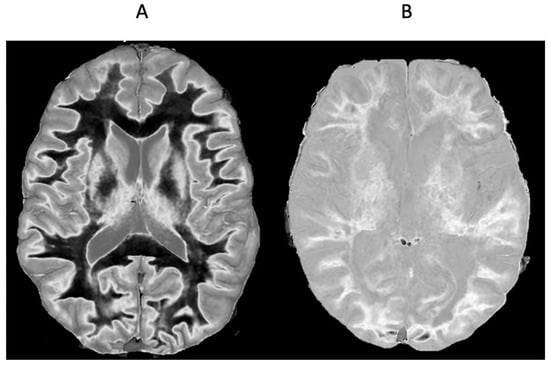

Figure 11 shows narrow mD dSIR images in a normal adult control (Figure 11A) and in a 77-year-old patient with MS (Figure 11B) during a relapse. In addition to the whiteout sign, there is a loss of contrast between gray and white matter in the thalamus of the patient (Figure 11B). Also, the heads of the caudate nuclei, as well as the insular and peripheral cortices, appear isointense with CSF on the dSIR image. These are grayout signs. No evidence of a whiteout sign or grayout signs was seen on the corresponding T2-FLAIR images.

Figure 11.

Skull-stripped images of a normal control (A) and 77-year-old patient with MS during a relapse (B). There is low signal in the normal white matter in (A) and a whiteout sign in (B). In addition, the gray matter in the thalamus and cortex has a uniform low signal and is nearly isointense with CSF. These are grayout signs. No evidence of a whiteout sign or grayout signs was seen on the positionally matched T2-FLAIR images.